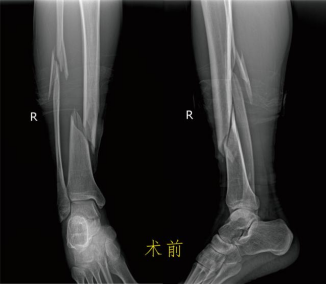

患者何某,41歲,月前因騎電動車時不慎摔倒,導致右小腿腫痛、活動受限,皮膚破裂流血不止,由120送至市一醫院經開區院區。攝DR顯示脛腓骨中下段螺旋型粉碎性骨折,骨折端明顯重疊移位。入院診斷:1.開放性脛骨下端骨折(右,粉碎性),2.腓骨骨折(右,粉碎性),3.小腿開放性傷口(右),4.高血壓。骨科醫師接診后立即在局麻下給患者進行右跟骨牽引術,起到矯正骨折畸形、恢復脛腓骨的長度及維持骨折的臨時穩定作用。經過治療處理,患者隨即表示疼痛緩解了很多,隨后在局部麻醉下對開放傷口進行了清創處理。 待患者右小腿開放傷口愈合后,檢查沒有發現紅腫熱痛、血常規白細胞增高等感染征象,進行脛骨骨折微創切開復位鋼板螺釘植入內固定。術后患者拆線出院,定期來院復查,2個月后逐步下地負重站立及行走,3個月可正常行走。